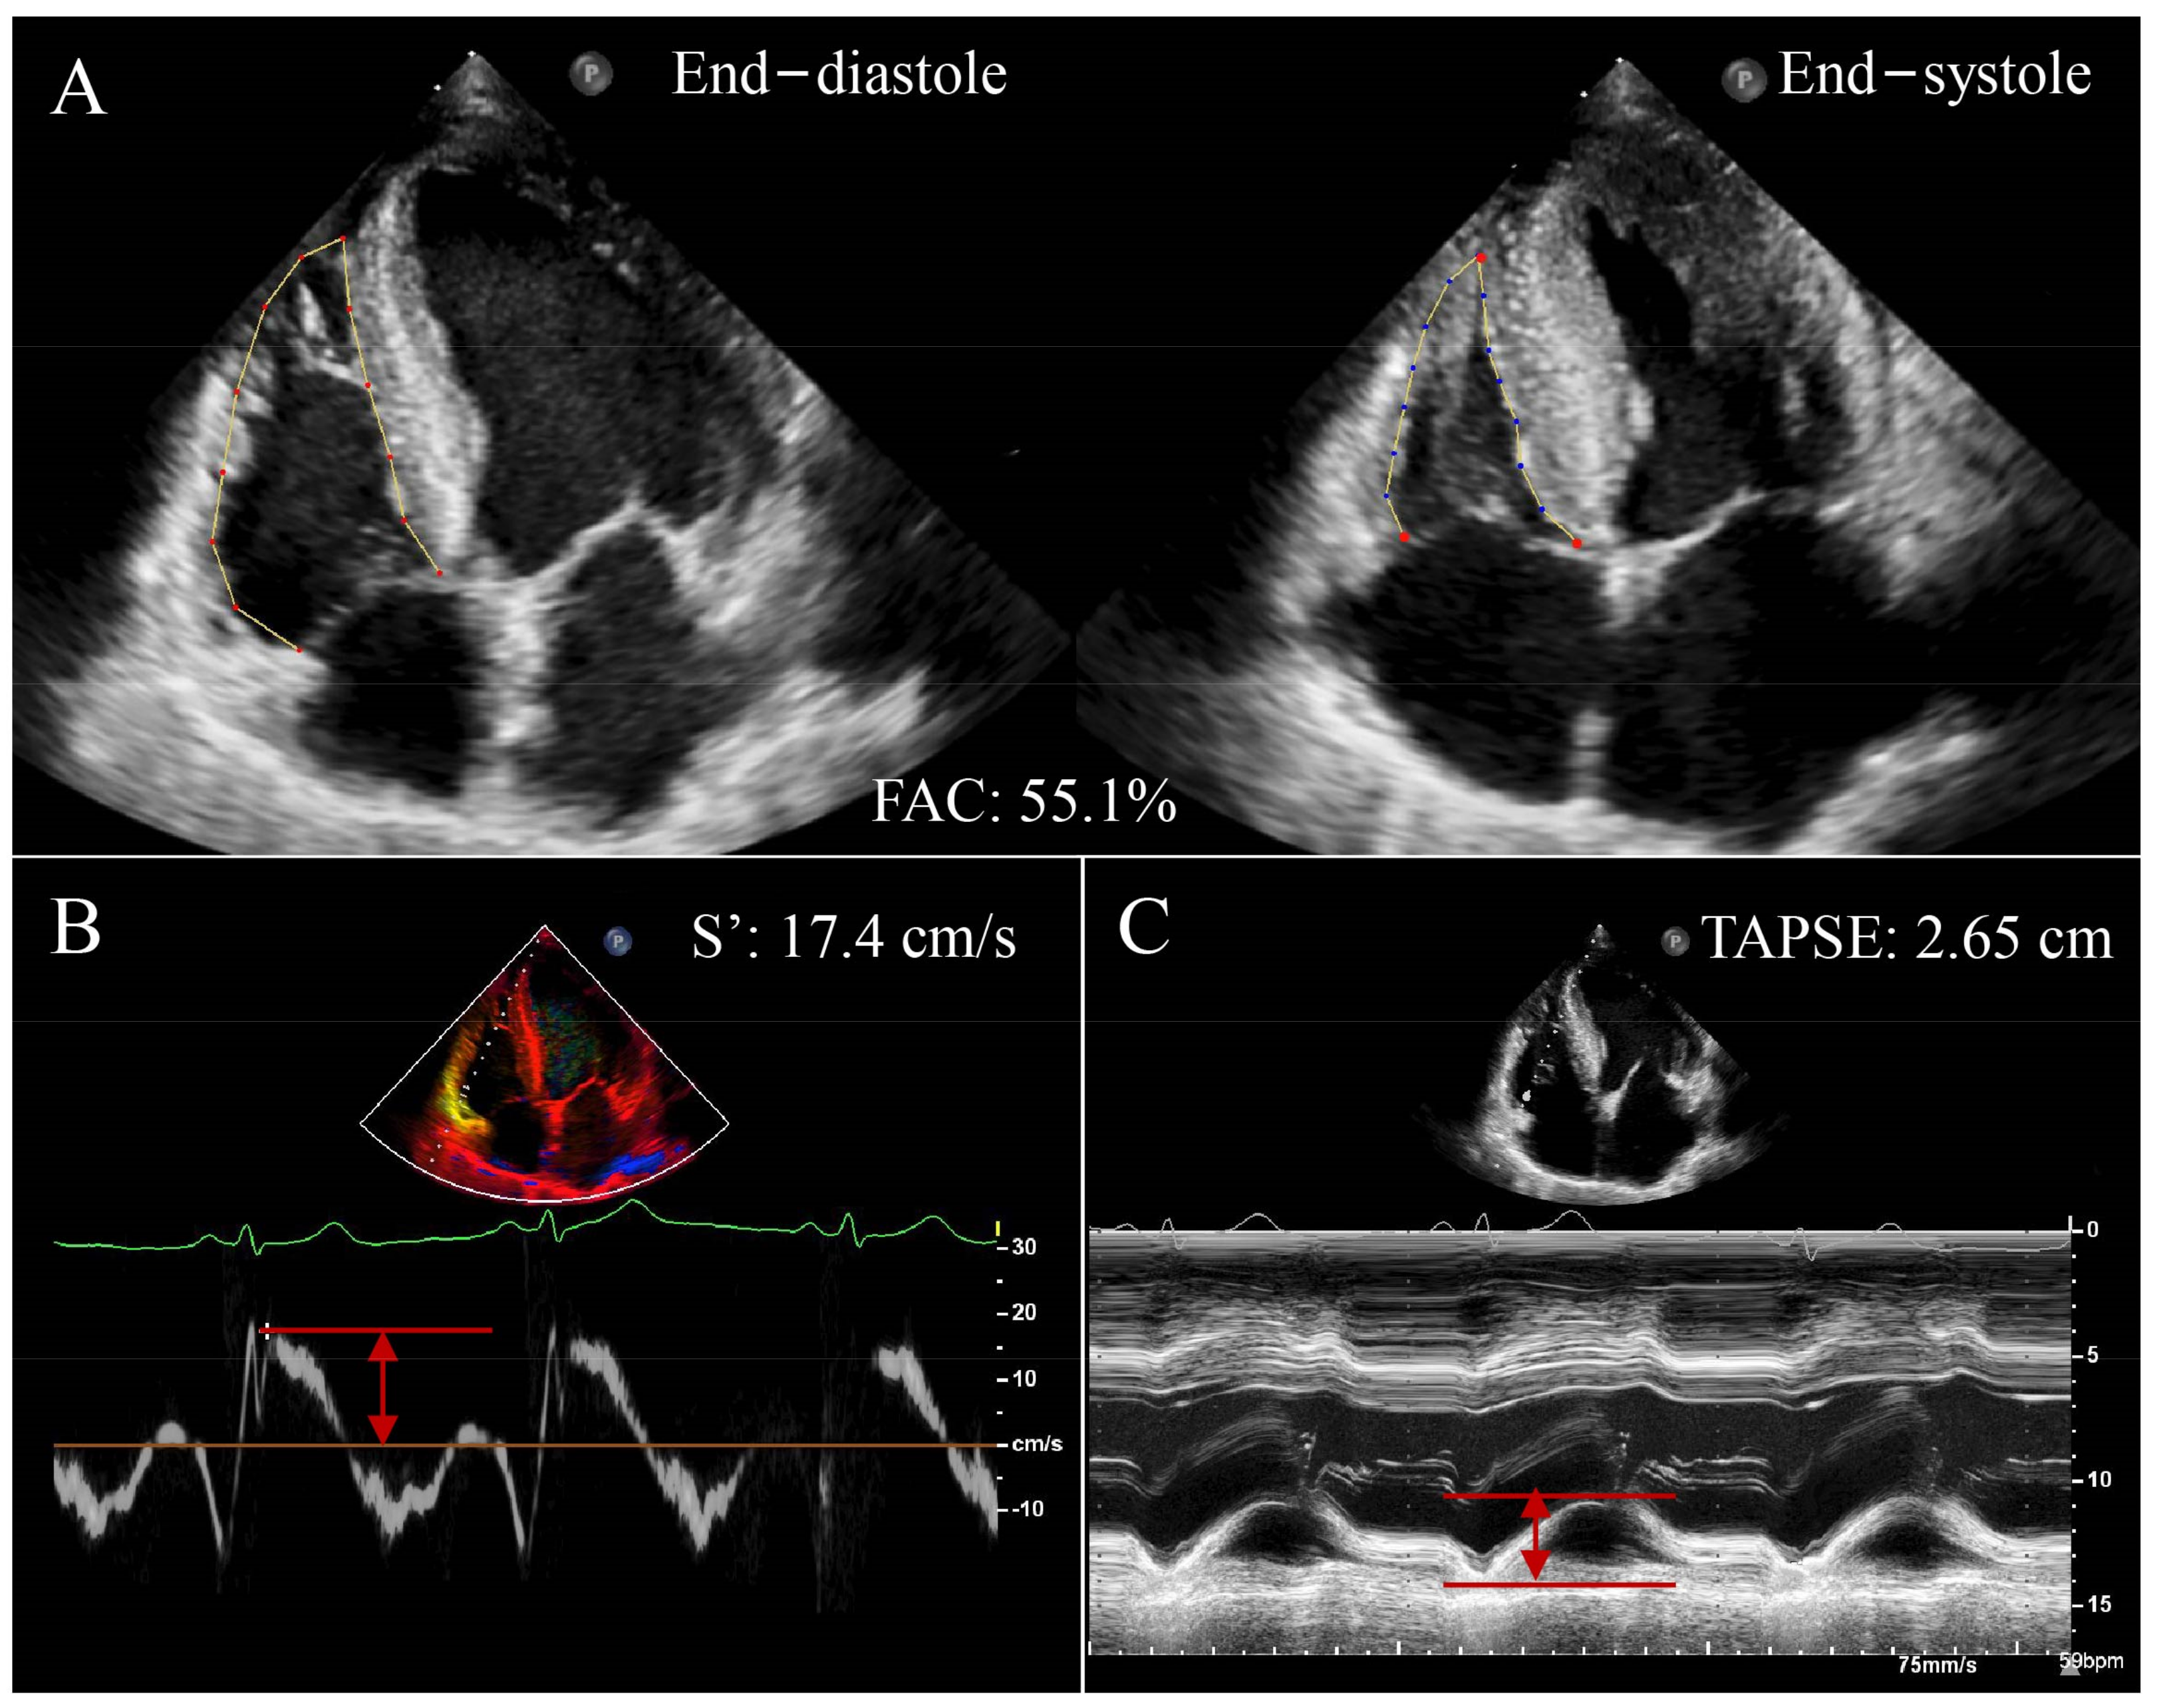

2.2.1. Tricuspid Annular Plane Systolic Excursion/Pulmonary Arterial Systolic Pressure

2.2.2. Tricuspid Annular Systolic Velocity/Right Ventricular Systolic Pressure

2.2.3. Right Ventricular Fractional Area Change/Right Ventricular Systolic Pressure